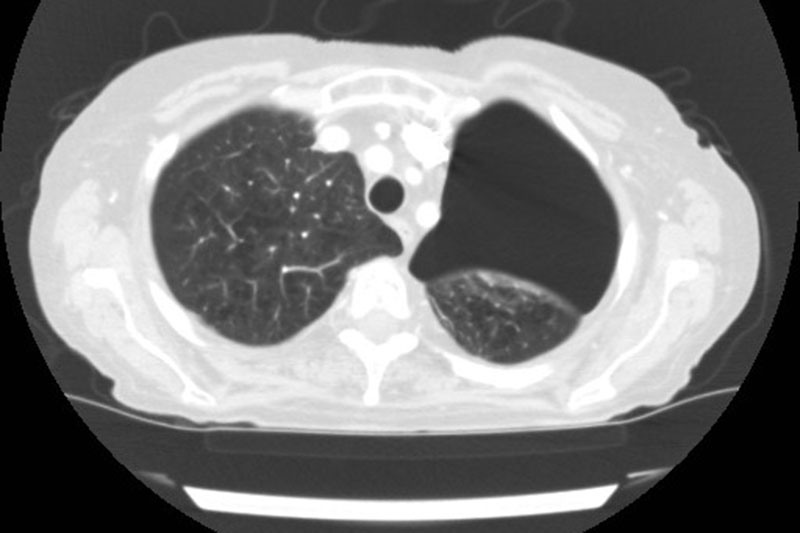

Window/Level

optimized for soft tissue

optimized for lung

optimized for bones

All viewers support this!